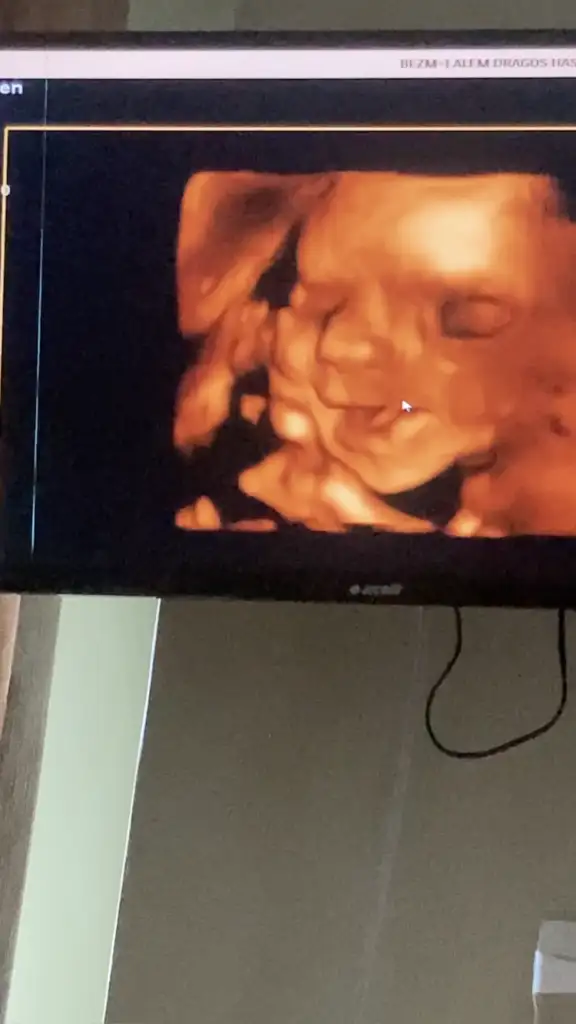

artık 15 de bir gidicem artık, benim uzunluktan ziyade kafa pozisyonu çok çok aşağıda. O yüzden yüzünü görmek imkansız gibi bir şeymiş artık